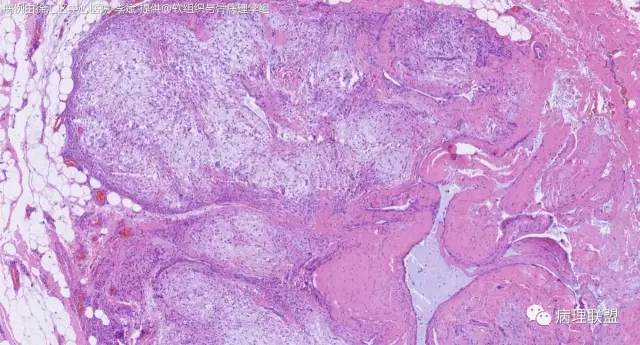

关节旁粘液瘤,肿瘤中间明显有腱鞘囊肿结构,又发生在关节处!强烈提示为关节旁粘液瘤,部分病例可以呈分叶结构!平时多加观察腱鞘囊肿囊壁常可见粘液变性!范围一广就成粘液瘤样。

取材时我以为是腱鞘囊肿,片子出来这样@周泉

@周泉 周老师您好,李斌老师第一个病例里细胞都是上皮样的包浆宽的,嗜酸,粘液瘤细胞细胞梭的星形的,所以我考虑是神经鞘的了,您觉得粘液瘤细胞也可以这种形态吗?

@左淑英 部分应该是组织细胞